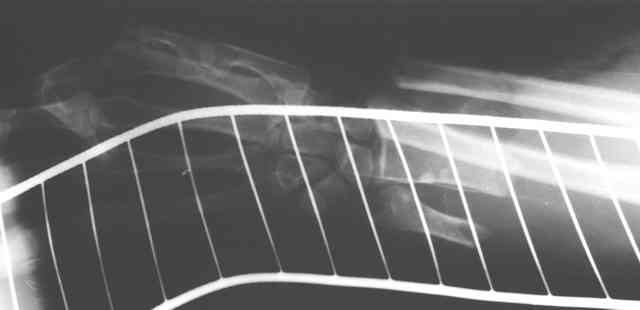

Травма 24 Октября этого года. Диагноз: Неполный травматический отрыв нижней трети предплечья. Выполнено: ПХО открытого перелома, фасциотомия, ЧКДО, шов лучевой артерии. Размозженые мышцы-сгибатели кисти и пальцев экономно иссечены - не сшивались. Спустя месяц выполнена резекция 2,5 см некротизированного конца проксимального отломка лучевой кости. На сегодняшний день по ладонной поверхности предплечья с переходом на наружний край имеется рана с дефектом мягких тканей, выполненная грануляциями с дна и с краев.

По рентгенограммам не видно дефекта лучевой кости после резекции 2,5

см (или снимки до того?).

Прошу прощения - не указал, что после резекции лучевой кости рентгенобследование больной еще не проводилось. На фотогрфиях раны вертикальными черными полосами показаны границы дефекта лучевой кости.